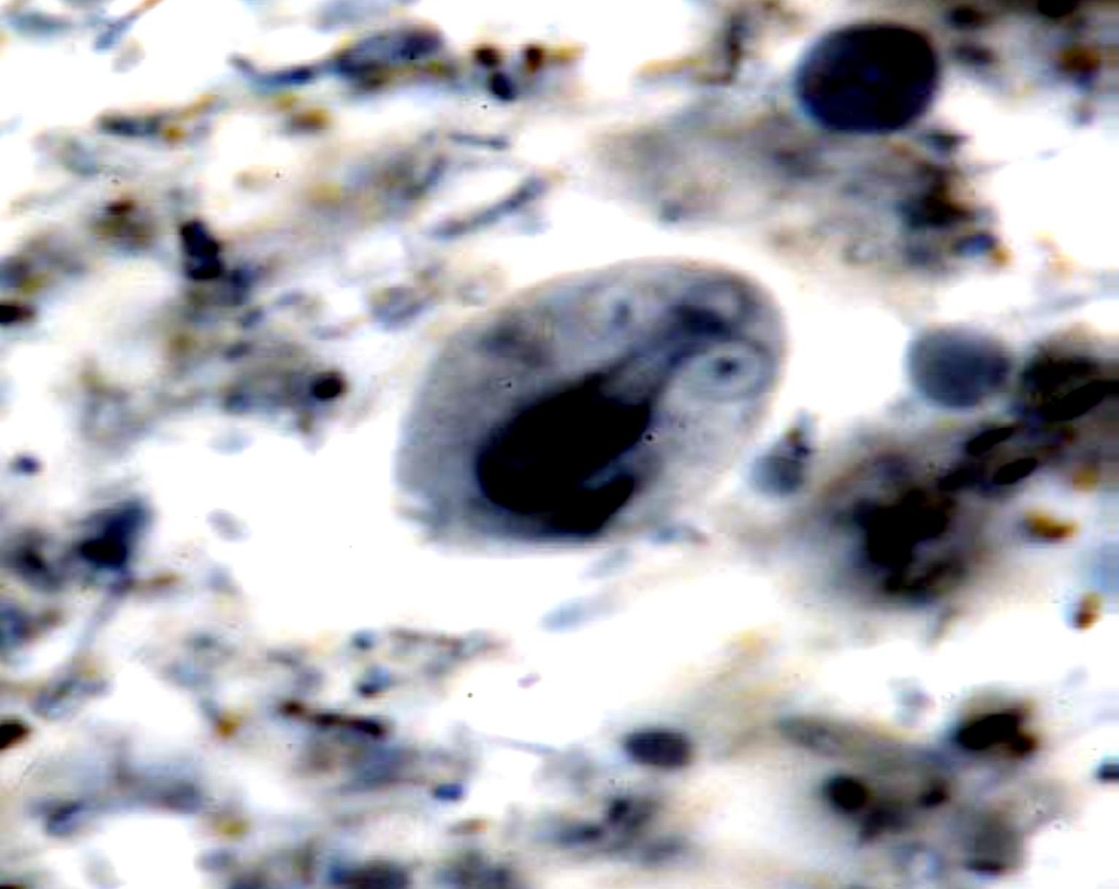

Trophozoite of Giardia lamblia